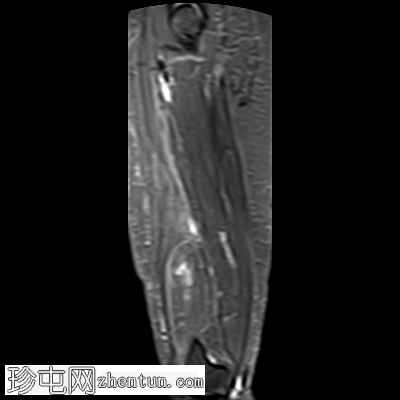

矢状位

T1加权像

STIR序列

可见一较大的、边界清晰的肌内肿块,主要累及股内侧肌及部分股中间肌。

病灶大小:4.3 x 5.2 x 12.6 cm(前后径 x 横径 x 头尾径)

信号特征:

T1加权像:均匀高信号,与皮下脂肪信号相同

T2加权像:均匀高信号,与皮下脂肪信号相同

PD脂肪抑制/STIR序列:信号均匀抑制,呈低信号,与皮下脂肪信号相同

未见内部增厚或结节状非脂肪性间隔,也未见强化实性成分。

边缘:光滑,呈分叶状,有一层薄的纤维包膜。

邻近结构:未见皮质凹陷、骨髓水肿或侵犯。

未见筋膜破裂、肌肉浸润或周围水肿。

以上特征符合良性肌内脂肪瘤的诊断。